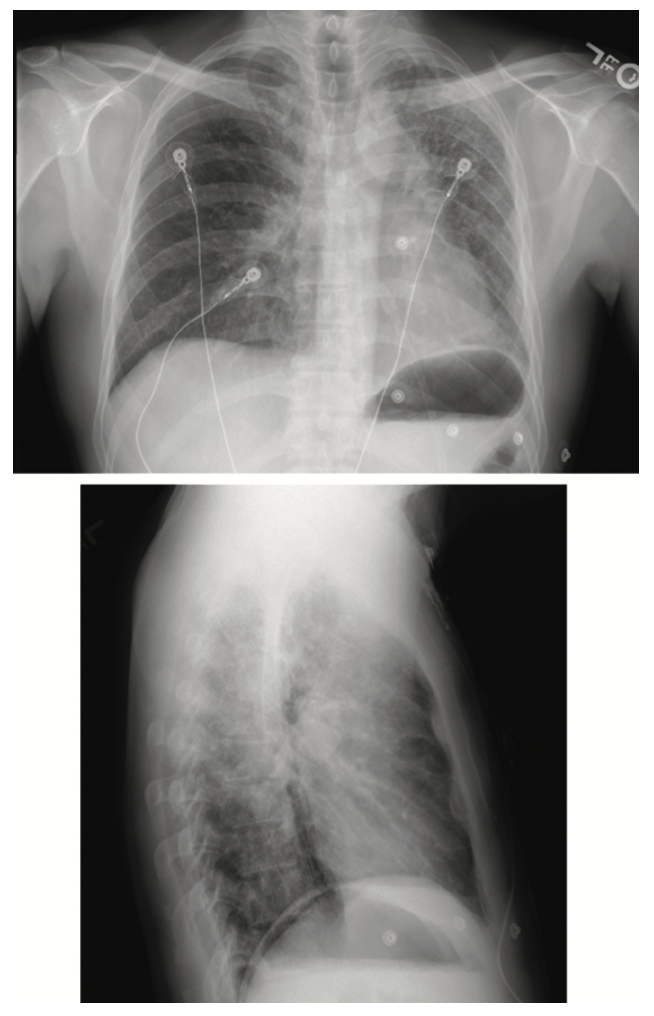

The patient’s initial electrocardiogram (ECG) of 12/2020 showed normal axis and nonspecific ST changes (Figure 1A). An ECG on 8/2021 showed rightward axis and right atrial enlargement, early repolarization changes, and diffuse ST-elevations in leads II, III, aVF, and V3-V6 (inferolateral and septal) with accompanying ST-depressions suspicious for possible pericarditis (Figure 1B). His chest x-ray demonstrated scarring and fibrotic changes most prominent in the left upper lung (Figure 2). A chest CT revealed fibrosis in the left upper lung (Figure 3A-B) greater than the right and persistent though improved peripheral ground-glass opacities. Transthoracic echocardiogram during hospitalization demonstrated a normal left ventricular ejection fraction (52%-55%) with mild tricuspid regurgitation, right ventricular systolic pressure 25-30 mmHg, and a normal inferior vena cava (IVC).